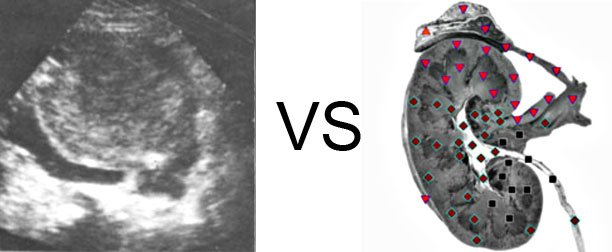

Vector Biofeedback PK Ultrasound Study